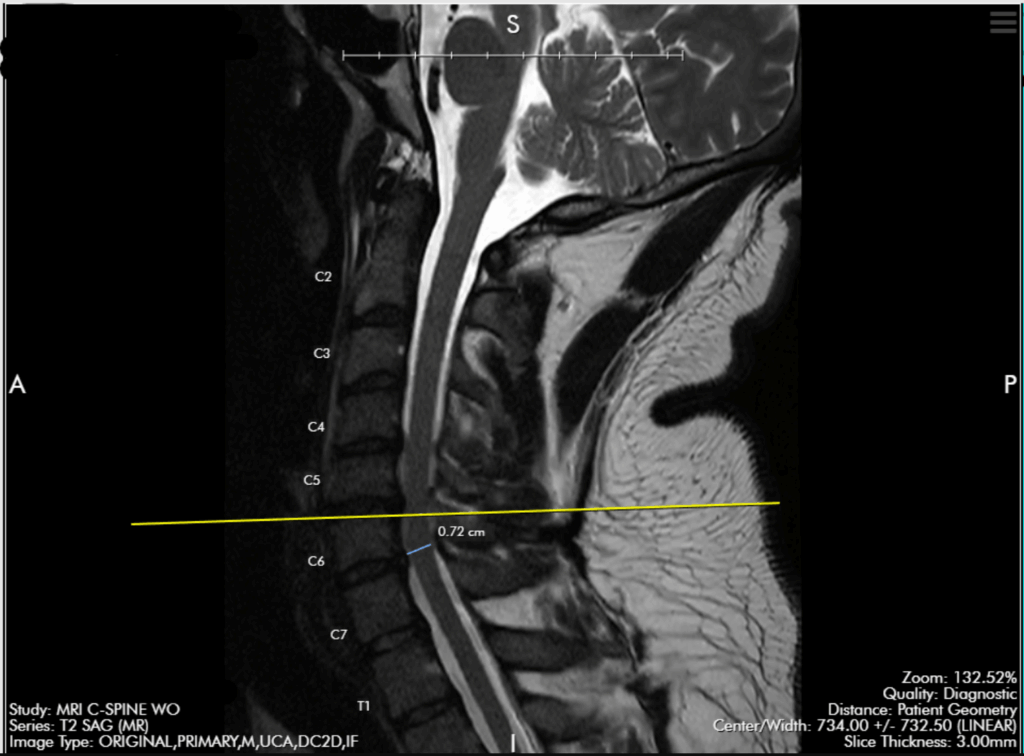

Anterior Cervical Disc Replacement